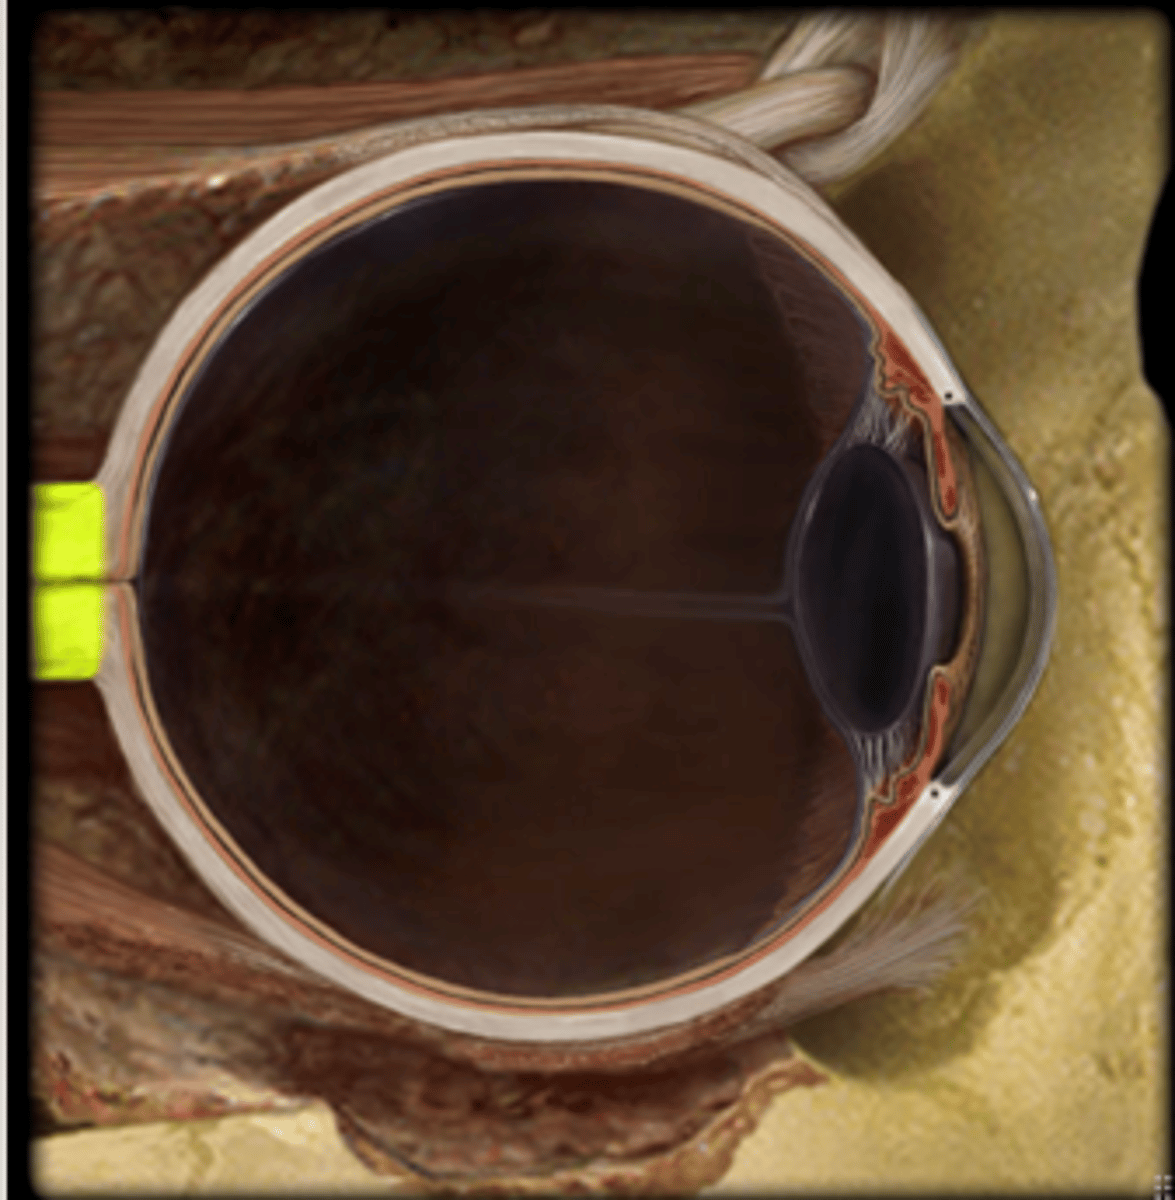

Eye

anterior chamber

posterior chamber

choroid

ciliary body

cornea

iris

lens

pupil

Sclera

suspensory ligament of eye

optic nerve

vitreous humor

soft, jelly-like material behind the lens in the viterious chamber, helps maintain shape of eyeball